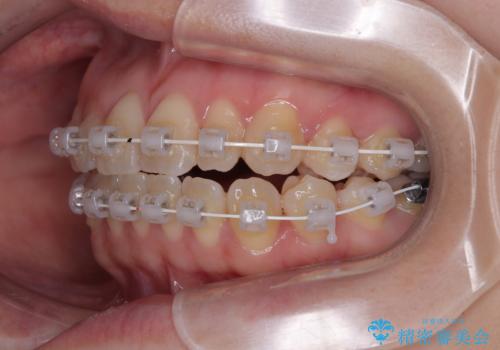

- 矯正装置

- 審美装置

治療方法についてご説明したところ、

できるだけ早く歯並びを整えたい

マウスピース矯正は装着時間や自己管理に不安がある

という患者様のご希望を踏まえ、プラスチックブラケット+コーティングワイヤーを用いたワイヤー矯正を選択しました。

この方法は、

金属色が目立ちにくく審美性が高い

確実に歯を動かせるため治療計画が立てやすい

といったメリットがあります。